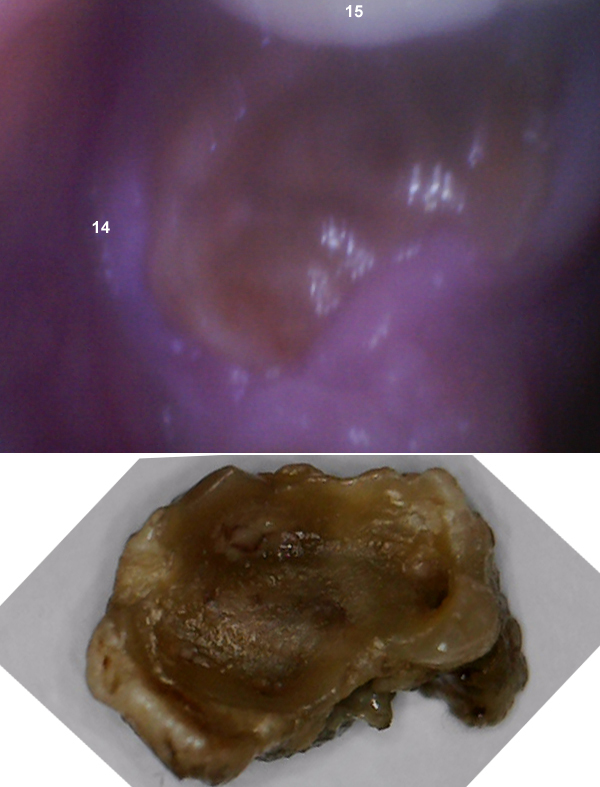

Bone has been shedding

This bone exfoliated in July 2015

/Picture%20040.jpg)

Abscess

Beginning of 2019 tooth 14 started internal resorption. The entire crown dissolved.

The remainder was pulled with necrotic bone attached.

This is at the base of the crown

These are the roots

After the tooth was removed a pyogenic granuloma or antral polyp appeared but resolved itself in 60 days.